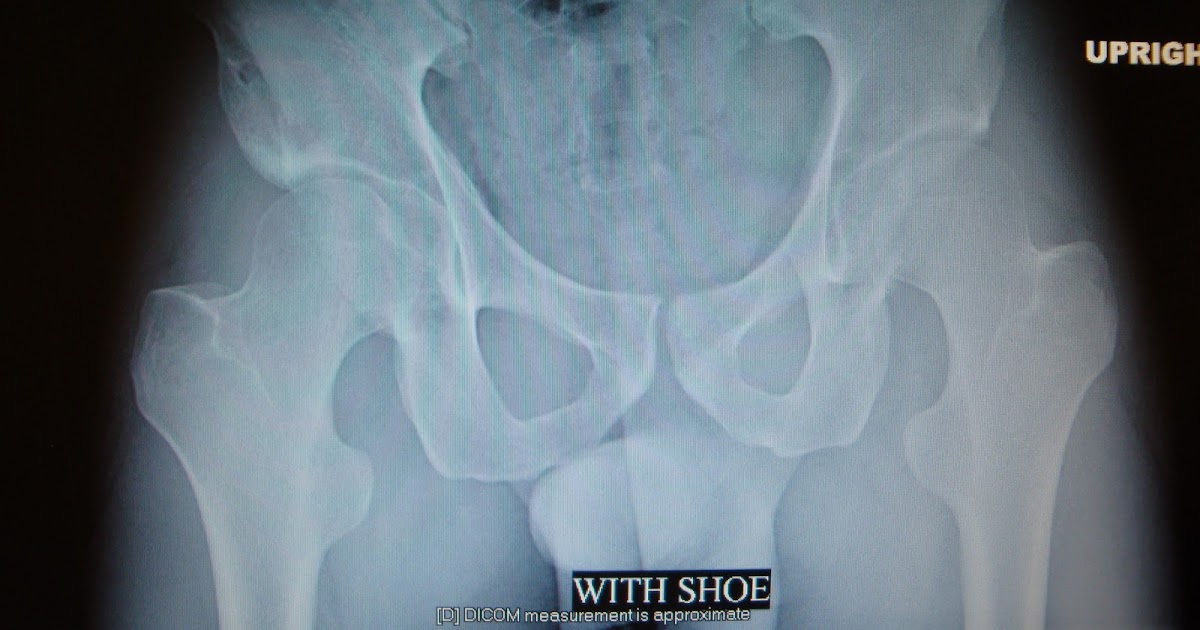

Functional Short Leg . leg length discrepancy, or as it has been alternatively termed, the short leg syndrome, is by far the most important postural. what is a leg length discrepancy? Some examples include conditions where the foot turns outward, or the pelvis is misaligned. It is a unilateral asymmetry of the lower extremity without any shortening of the osseous. 30 structural and functional limb shortages. the objective is to define functional short leg, how it differs from anatomic lli and explore any association. short leg syndrome (sls) is better known in the medical community as leg length discrepancy. In the simplest terms, one who suffers from sls will have one leg that is. Sometimes athletes who run on hard surfaces develop foot problems that lead to functional sls. functional sls is where one leg becomes shorter due to the mechanics of the lower body. the functional short leg is caused by a soft tissue contracture or foot deformity.

the objective is to define functional short leg, how it differs from anatomic lli and explore any association. what is a leg length discrepancy? It is a unilateral asymmetry of the lower extremity without any shortening of the osseous. short leg syndrome (sls) is better known in the medical community as leg length discrepancy. Sometimes athletes who run on hard surfaces develop foot problems that lead to functional sls. In the simplest terms, one who suffers from sls will have one leg that is. leg length discrepancy, or as it has been alternatively termed, the short leg syndrome, is by far the most important postural. the functional short leg is caused by a soft tissue contracture or foot deformity. Some examples include conditions where the foot turns outward, or the pelvis is misaligned. functional sls is where one leg becomes shorter due to the mechanics of the lower body.